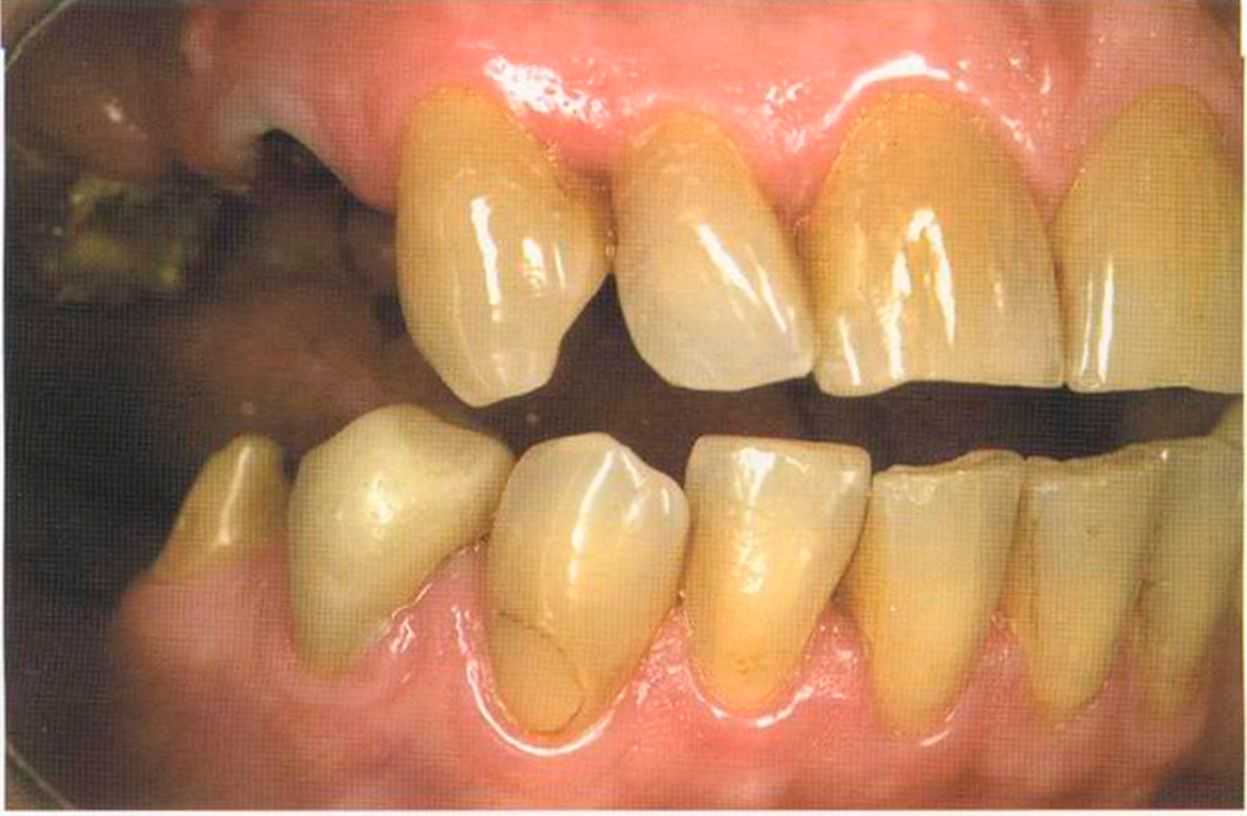

Этот пациент — португалец. Он всю жизнь имел такое положение зубов. Небнорасположенный боковой резец теперь необходимо удалить, а затем воссоздать как эстетику, так и функцию в области фронтальной группы зубов. Планируется изготовить коронки In-Ceram в области 11 и 21 и соединить их вместе из-за увеличивающейся подвижности зубов.

Препарирование, проводимое доктором Риссе, оценивается как очень сложное. Режущие края центральных резцов сильно дивергируют, что создает неудобство при формировании хорошего уступа.

Из-за сильной протрузии центральных резцов на них всегда падает итого света, и они кажутся очень большими. Чтобы смягчить этот эффект, мы выбрали более темный цвет для реставрации.

Фото сверху и слева: отличный результат препарирования зубов с уже уложенными нитями для снятия оттиска.